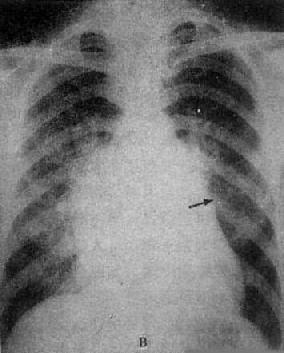

图3-2-16 二尖瓣关闭不全并狭窄

心增大呈二尖瓣型,右心室增大,肺动脉

段突出,左心耳增大,有肺瘀血

图3-2-17 慢性肺原性心脏病

心呈二尖瓣型,右心室增大,肺动脉突出,但无左心耳增大。肺动脉扩张,尤以右下肺动脉为明显,有肺门截断现象,说明有肺动脉高压。肺纹理增强,肺透明度增加,膈平而低,说明有慢性支气管炎和肺气肿